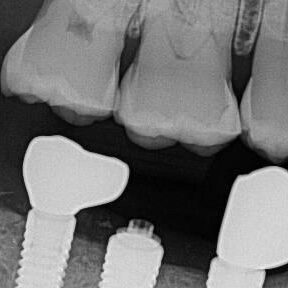

ULTRASONICS: Complications of Abutment Screw Retrieval Secondary to Prior Ultrasonic Attempts

There has been much written on the use of ultrasonics in retrieving fractured screw fragments, which I didn’t think a lot about until May of 2023, as it has not been a part of my fractured screw retrieval algorithm.